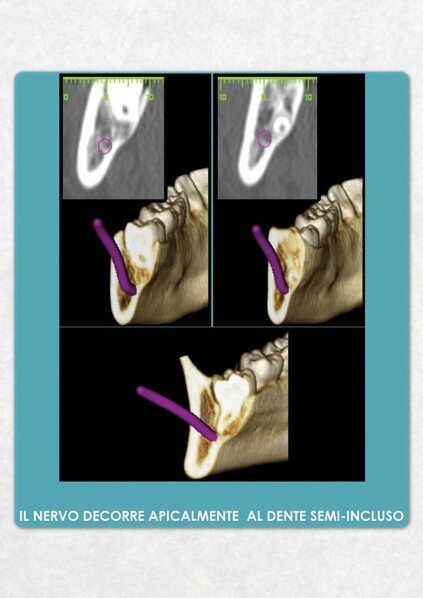

La diagnostica dei casi complessi di chirurgia orale ed implantologia è realizzata, a partire da una TAC dentale a cui si sottopone il paziente, mediante l'utilizzo del software computerizzato ONE SCAN 3D. Attraverso questo programma è possibile ottenere una ricostruzione tridimensionale del mascellare/mandibola del paziente, identificare le strutture anatomiche di riferimento, valutare i tessuti duri e molli, pianificare l'inserimento degli impianti nell'osso disponibile e ottenere un valido consenso informato del paziente all'intervento chirurgico.

Questo approccio moderno e tecnologico consente all'odontoiatra di lavorare con la massima serenità,riducendo al minimo qualsiasi imprevisto in fase operatoria.